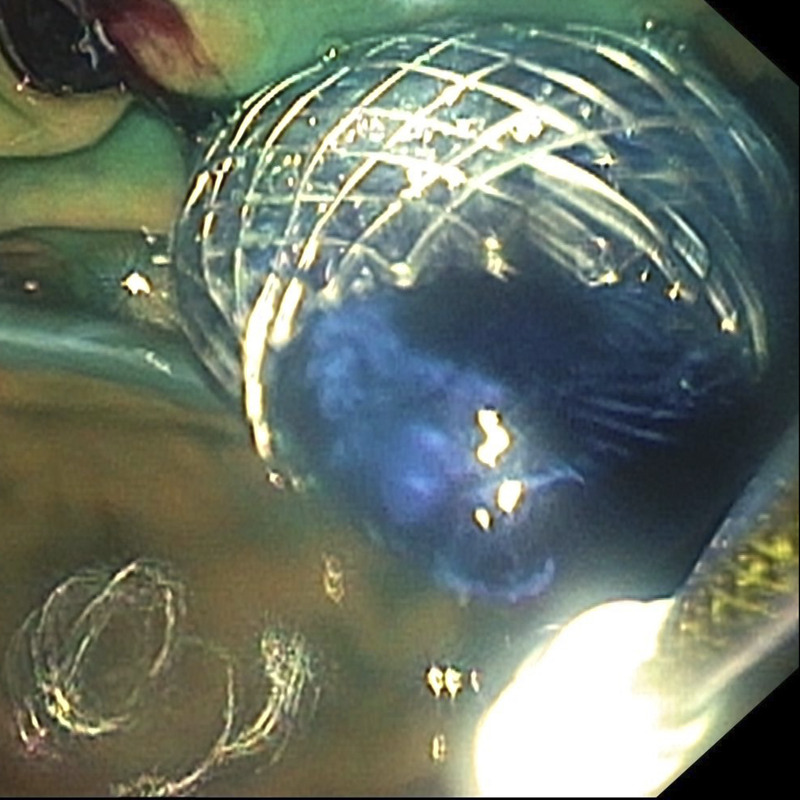

十二指肠支架置入术后恶性十二指肠梗阻复发:eus引导胃空肠吻合术成功治疗(附视频)。

Recurrence of malignant duodenal obstruction following duodenal stenting: successful management through EUS-guided gastrojejunostomy (with videos).